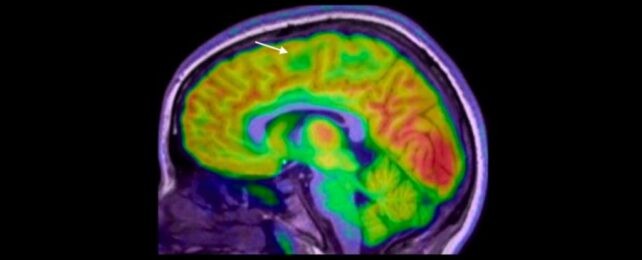

An artificial intelligence tool trained to read brain scans is helping doctors spot tiny, blueberry-sized brain malformations in children with epilepsy — lesions that are often missed on standard MRI. Structural abnormalities cause about three in ten epilepsy cases, and many kids who could benefit from surgery are never considered because the lesions hide in plain sight. Researchers say this AI could help families access potentially life-changing surgery sooner, offering a new thread of hope where none seemed possible.

Tiny brain lesions can escape detection on MRI, particularly those tucked at the bottom of a brain fold. In the study, 80% of the children had prior MRI results that were normal, suggesting many surgical candidates were overlooked before artificial intelligence was involved. The scale and subtlety of these abnormalities mean a missed diagnosis can delay life-changing treatment.

Led by paediatric neurologist Emma Macdonald-Laurs at the Royal Children’s Hospital in Melbourne, the team trained an AI tool on pediatric brain images to detect lesions the size of a blueberry or smaller. When the AI analyzed both MRI and PET scans, its performance reached 94% in one test group and 91% in another. Of 17 children in the first group, 12 had surgery to remove their brain lesions, and 11 are now seizure-free. The researchers plan to test the detector in more real-life hospital settings with undiagnosed patients.